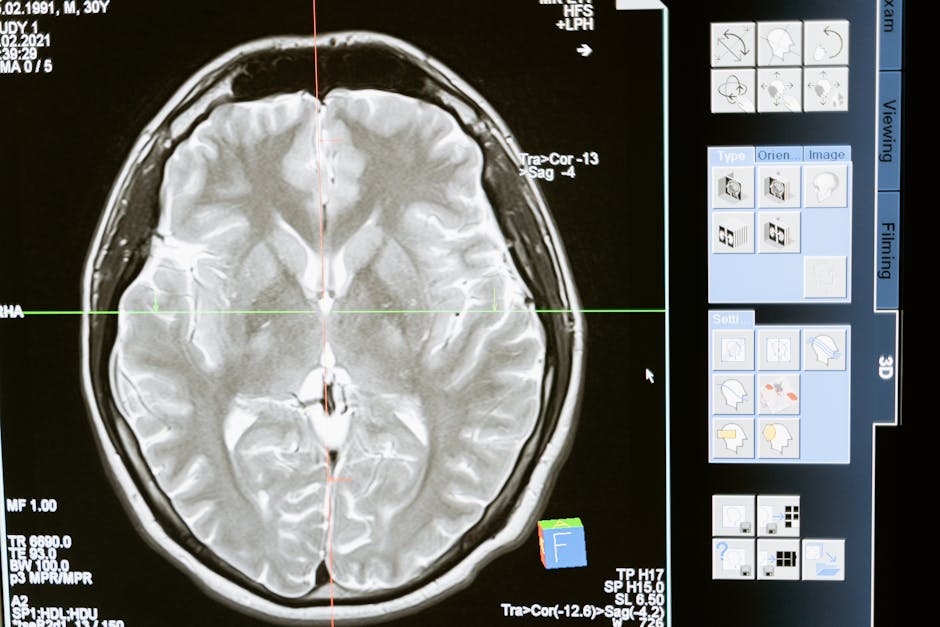

If you've ever wondered why so many British families turn to crowdfunding campaigns when cancer strikes, the story of glioblastoma—the most common form of malignant brain tumour in adults—offers a revealing case study. Each year, about 3,200 to 4,500 people in the UK receive this diagnosis. For most, the NHS provides surgery, radiotherapy, and chemotherapy as part of a standard protocol. Yet survival rates remain grim: the median is 12–15 months, and fewer than 5% live beyond five years.